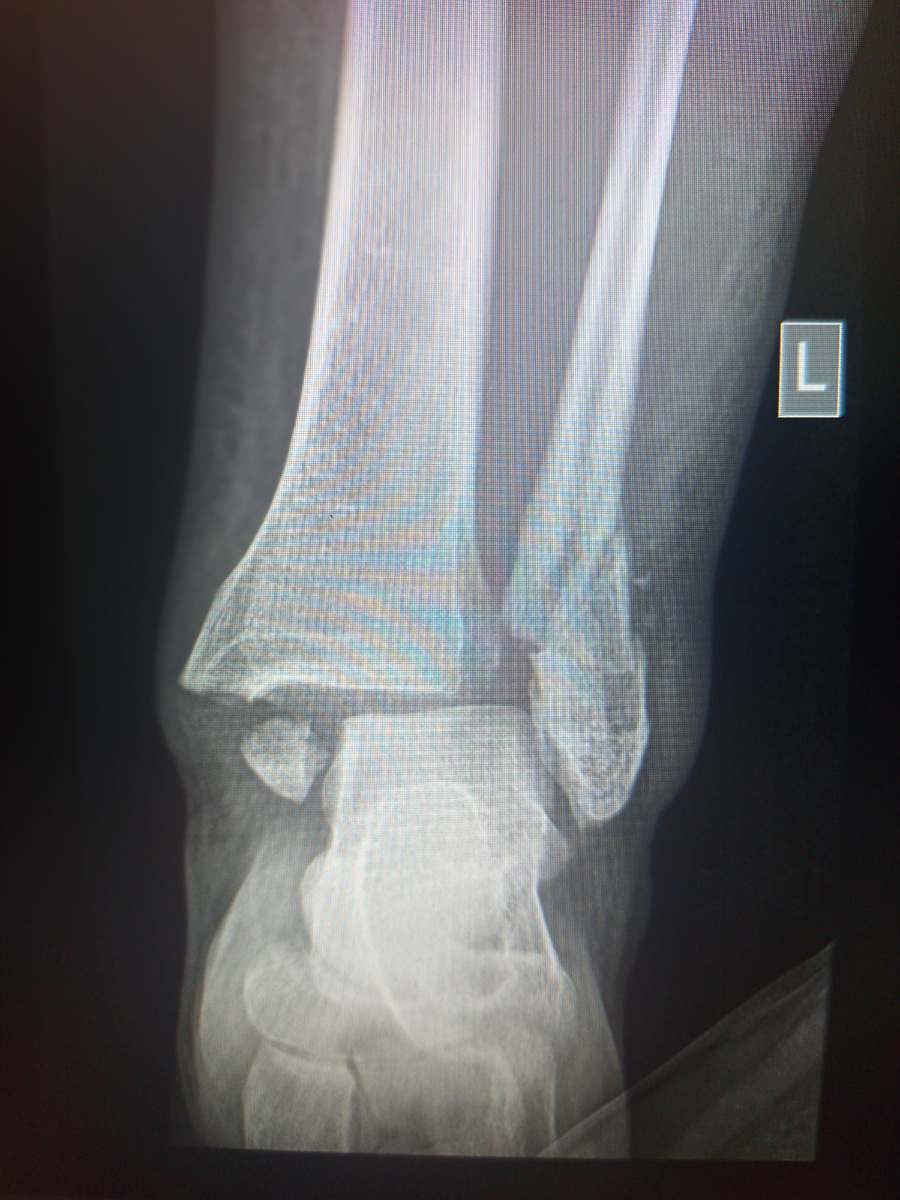

Привезли на сидячей каталке женщину,56 лет, на снимок голеностопа.

Женщина с красиво уложенными волосами, праздновала что ли?

–А что случилось?

–Вы не поверите! Да и кому рассказать–тоже. Я сама не местная, приехала на свадьбу к племяннице, пошла в салон на укладку, причесали меня красиво , накрасили, по ступенькам салона спускаюсь–и на тебе! Просто на ровном месте оступилась!

Да уж, вместо свадьбы –больница скорой помощи. Конечно, ее госпитализировали.